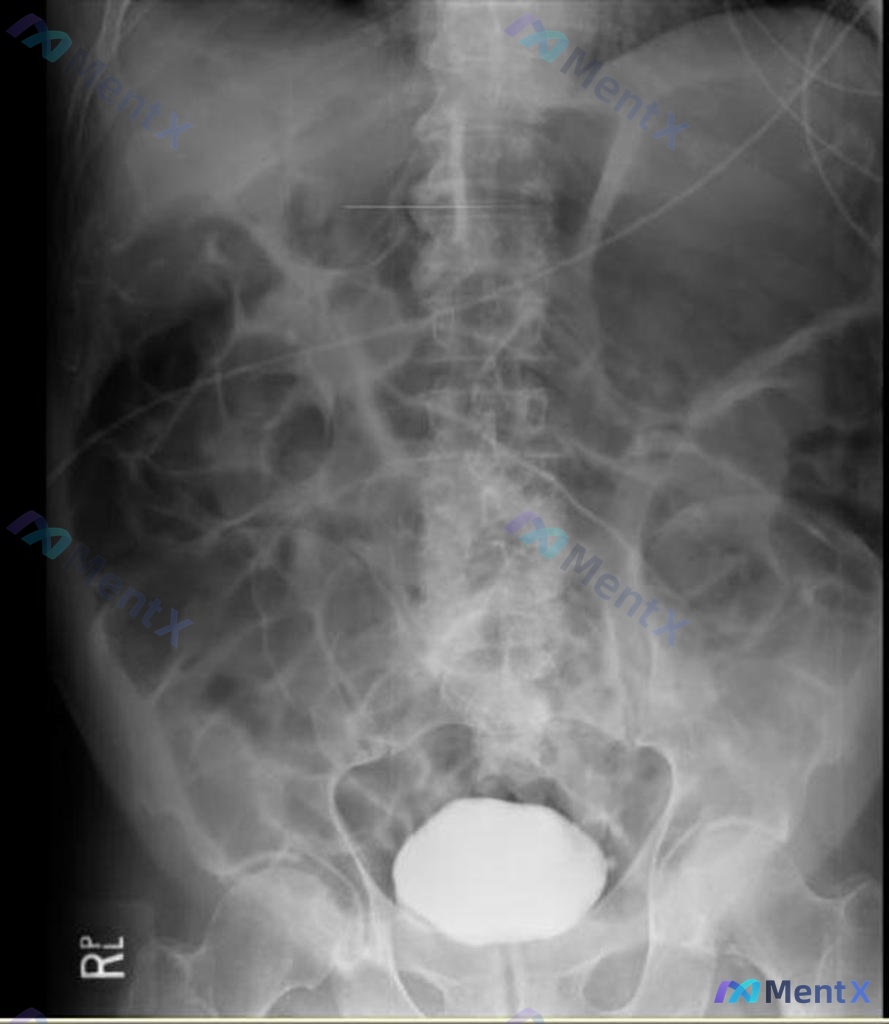

- 腹部X线:可见明显小肠扩张、充气,多个气液腔影;膈下未见明显游离气体;可见引流管/胃管影;盆腔见椭圆形高密度影(考虑膀胱造影剂可能)